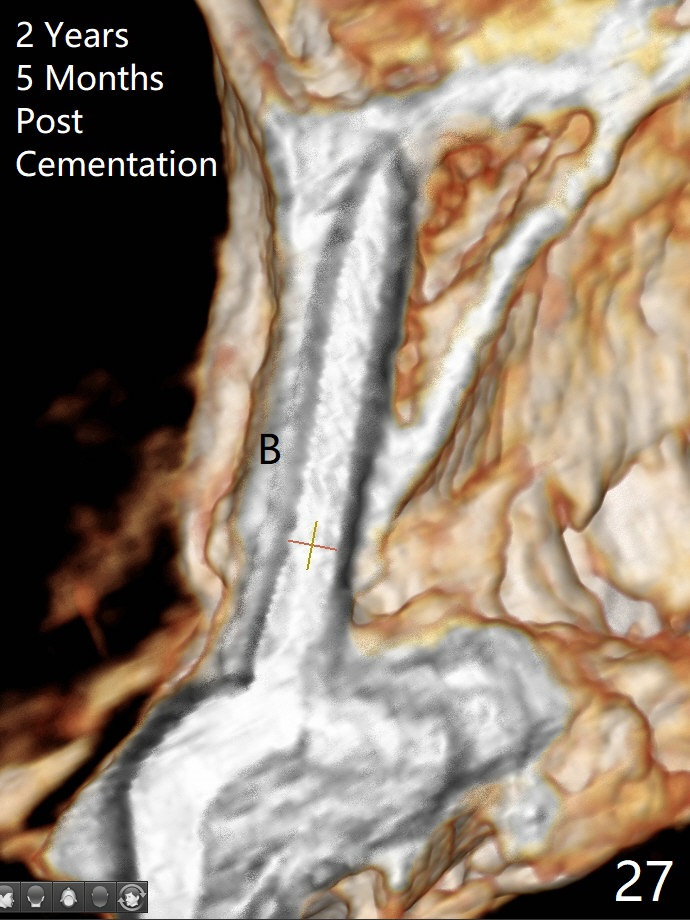

Since the ridge at #7 is ~ 4 mm, a 2.5x14 mm 1-piece implant is placed (Fig.8) after 1.2 mm (Fig.7), and 1.5 mm drills at 12 mm and 2 mm drill at 8 mm.  Later the implant is placed deeper (Fig.10).  There is no bone loss 7 or 12 months postop, respectively (Fig.11,12).  After Diode gingivectomy, there is papillary formation (Fig.13).  No provisional is provided after impression (with the abutment torqued at #6) for oral hygiene.  With access holes at #6 and 7, crowns are bonded with minimal residual cement (Fig.14 <, which is removed later).  There is no hard (Fig.15,16) or soft (Fig.17 *) atrophy 26 months postop, i.e., 13 months post cementation, due to the presence of socket shield (Fig.15 <, as compared to Fig.1).  In fact the tooth #8 has mobility and fremitus (short root/poor crown/root ratio, Fig.16); occlusal adjustment is done 13 months post cementation.  The crown is dislodged 2 years 1 month post cementation; a prefabricated post is being tried in (Fig.18).  There is no atrophy, bone loss or infection at #6 (with socket sheath (*)) or 7 two years 5 months post cementation (Fig.20-27).